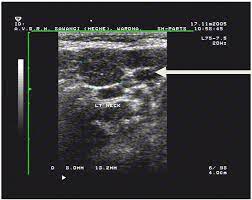

Thyroid Cancer It S Not In Your Head It S In Your Neck Cancerconnect

Thyroid Cancer It S Not In Your Head It S In Your Neck Cancerconnect from news.cancerconnect.com

An ultrasound may be used to check for certain cancers in various different ways. What an ultrasound can detect? 31 533 просмотра • 28 сент. Cysts or abnormal growths in the liver, spleen, or pancreas. Brook's personal experiences as a patient with throat they are also used to detect cancer and follow up its progression and response to therapy. Some genetic disorders, such as fanconi anemia, can increase the risk of developing precancerous lesions and cancers early in life (30). Sometimes the cancer cells can spread into the nearby lymph nodes. Ultrasound can detect abnormalities indicating cancer in breast, liver, etc., but a definite diagnosis requires further tests like ct or mri scan. However, ultrasound does not produce images with the same level of clarity or detail as a ct or mri scan, nor can it confirm a cancer diagnosis on its own. A scanner then detects this substance to produce images. Ultrasound image of a neck mass. For head and neck cancers, immunotherapy medications may act on a specific protein in immune. An ultrasound of the neck uses high frequency sound waves to create a live image from inside of a patient's body.